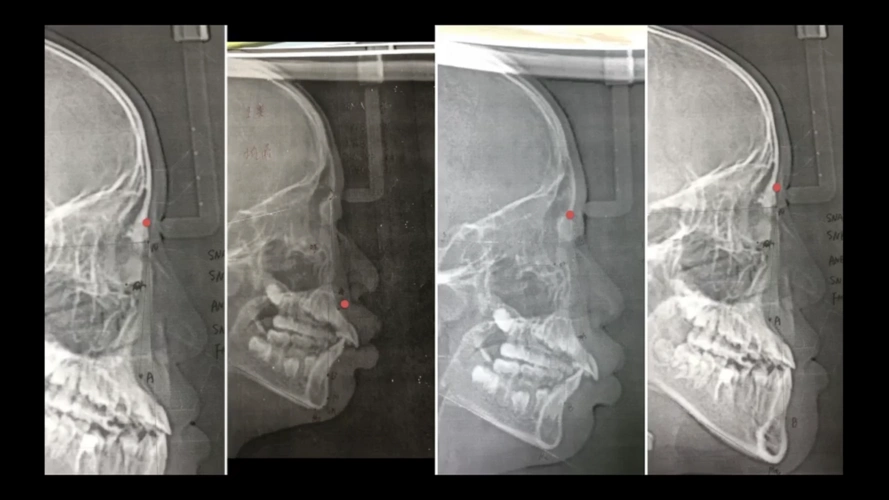

头颅侧位片的描绘与分析(二)微课 2020.07.14